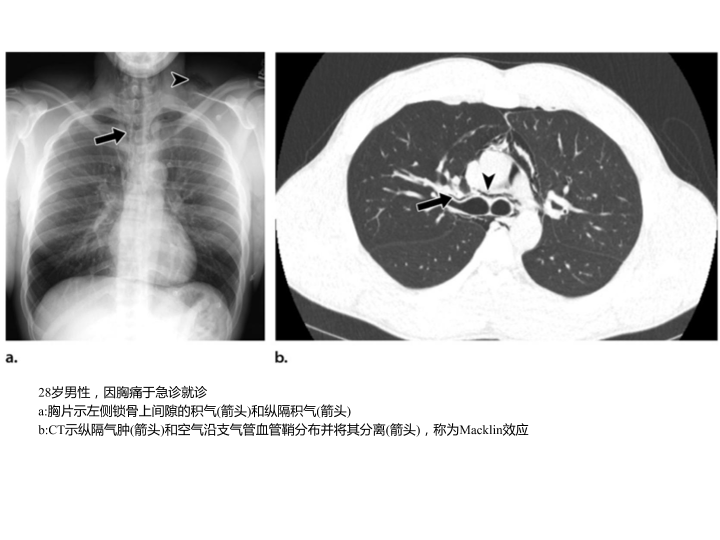

胸部外伤及胸腔积液处理